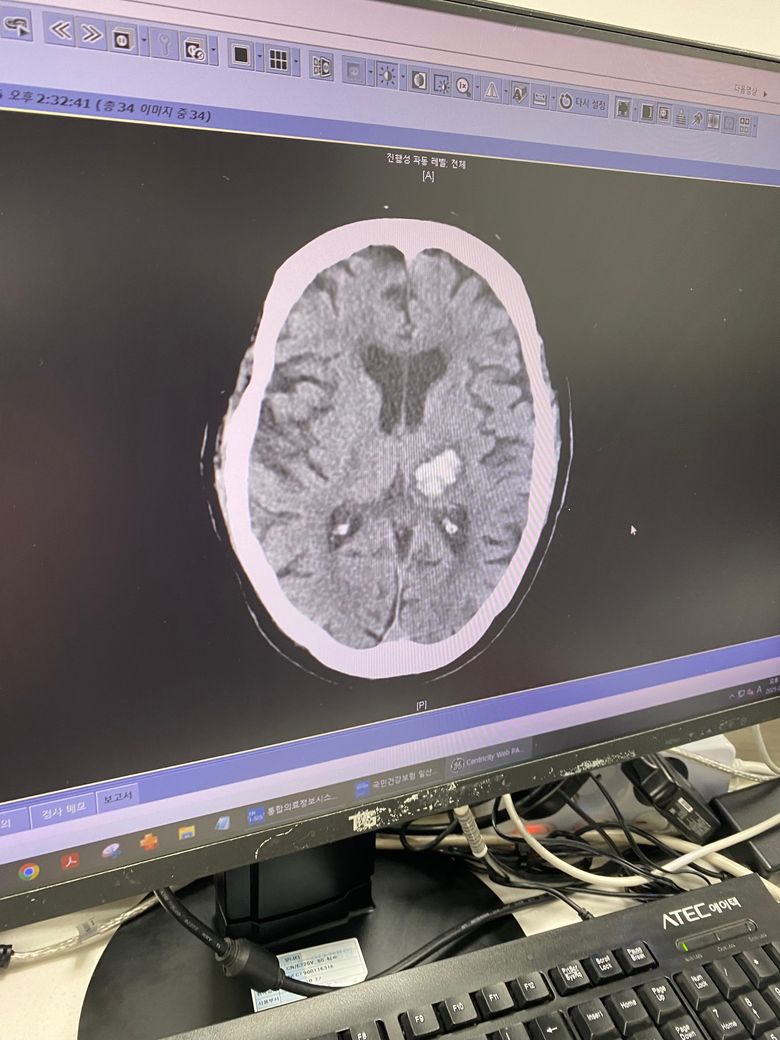

어머님이 뇌출혈로 쓰러지셨어요. . . .

어머니가 뇌출혈로 병원으로 이송하셨는데. .

바로 수술 한다고 했는데.

다시 보전적치료로 지켜보자고 하네요.

편마비가 오셨다가 지금은 감각이 살짝 있으신것 같긴한데. . 말은 잘 못하세요.

어머님의 갑작스러운 뇌출혈 소식에 얼마나 마음이 아프실지 짐작하기 어렵습니다. 수술 여부가 변경된 점과 어머님의 현재 상태 때문에 더욱 걱정이 많으실 텐데요, 뇌출혈의 경우, 출혈 위치와 크기, 환자분의 전반적인 건강 상태 등을 종합적으로 고려하여 치료 방법을 결정하게 됩니다. 보존적 치료는 출혈이 자연적으로 멈추고 뇌압이 안정될 수 있도록 돕는 방법이며, 편마비와 언어 장애는 뇌 손상 부위에 따라 나타날 수 있는 증상입니다. 현재 감각이 돌아오시는 징후가 있다는 것은 긍정적인 부분입니다.

뇌출혈의 수술 여부는 출혈의 양, 위치, 증가 양상 등을 종합적으로 평가하여 신경외과 의사가 판단하게 됩니다. 입원하셨으니 치료 잘 받으시기 바라겠습니다.